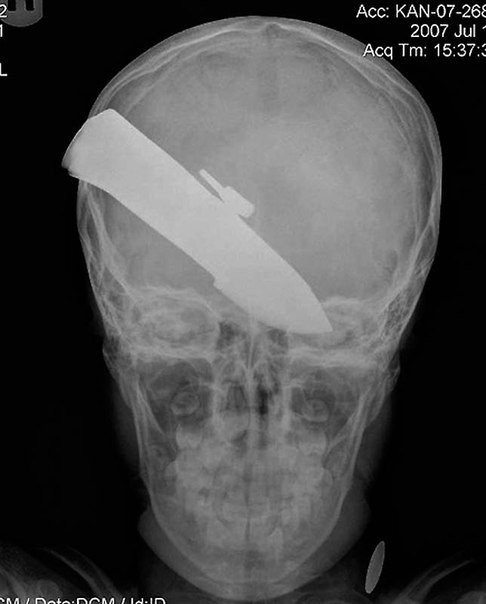

Самые причудливые рентгеновские снимки в истории медицины. Некоторые из них жуткие и пугающие, возможно часть из них вызовет у вас шок. Трудно поверить в то, что это правда, однако снимки говорят сами за себя.. 1) Череп китайского мужчины, который был уби8 写真